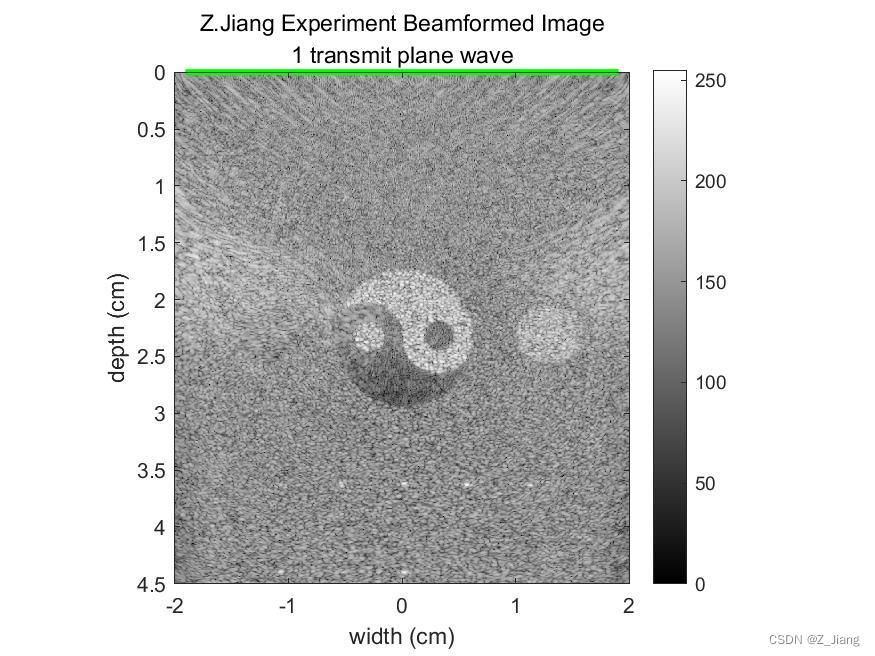

下面我做个极端例子,使用128晶元线阵探头,平面波发射,只做一次发射打开全部晶元,波束合成时,接收MLA=512,覆盖整个成像区域,情况如下

相同的情况,换作发散波,单次发射,打开全部晶元,MLA=512,覆盖全区域,结果如下

左:体模 中:单次全孔径平面波 右:单次全孔径发散波

扩散波与平面单次发射,全区域成像结果比较类似。我们可以发现,这两种发射由于成像区域内没有焦点,也就不存在无声区,即使我做到512的MLA覆盖4厘米的宽度,也不会出现暗黑的无声区域。另外,大家应该留意到MLA的BLOCK格子也不会存在。因为声压全场统一,不会由于不同的MLA线处声压强度,导致MLA线实际位置横向偏移,同时这种极端扫查情况下,帧速率(FPS)可以做到每秒几千甚至上万。可以把这样的优势用在需要高帧速的场景,更精细的运动追踪,时间解析度更高的造影等等。

但缺点也很明显,grating lobe伪影明显,信噪比低,分辨率差等。在实际系统设计上,我们肯定使用更小的孔径,更少的MLA,多次发射,降低FPS,来平衡图像品质。